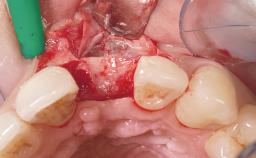

Late Placement of an Implant in a Maxillary Left Central Incisor Site

A 36-year-old female patient was referred for the replacement of the upper left central incisor (tooth 21), which had fractured. Although the tooth had been asymptomatic for many years, the crown began to loosen, at which time she presented to her dentist for an assessment. Teeth 21 and 22 had both been endodontically treated many years previously. She was a healthy individual and a non-smoker.

Bone Augmentation | Horizontal|Staged |

Augmentation Materials | Xenogenous|Membrane |

Soft Tissue Grafting | Simultaneous |